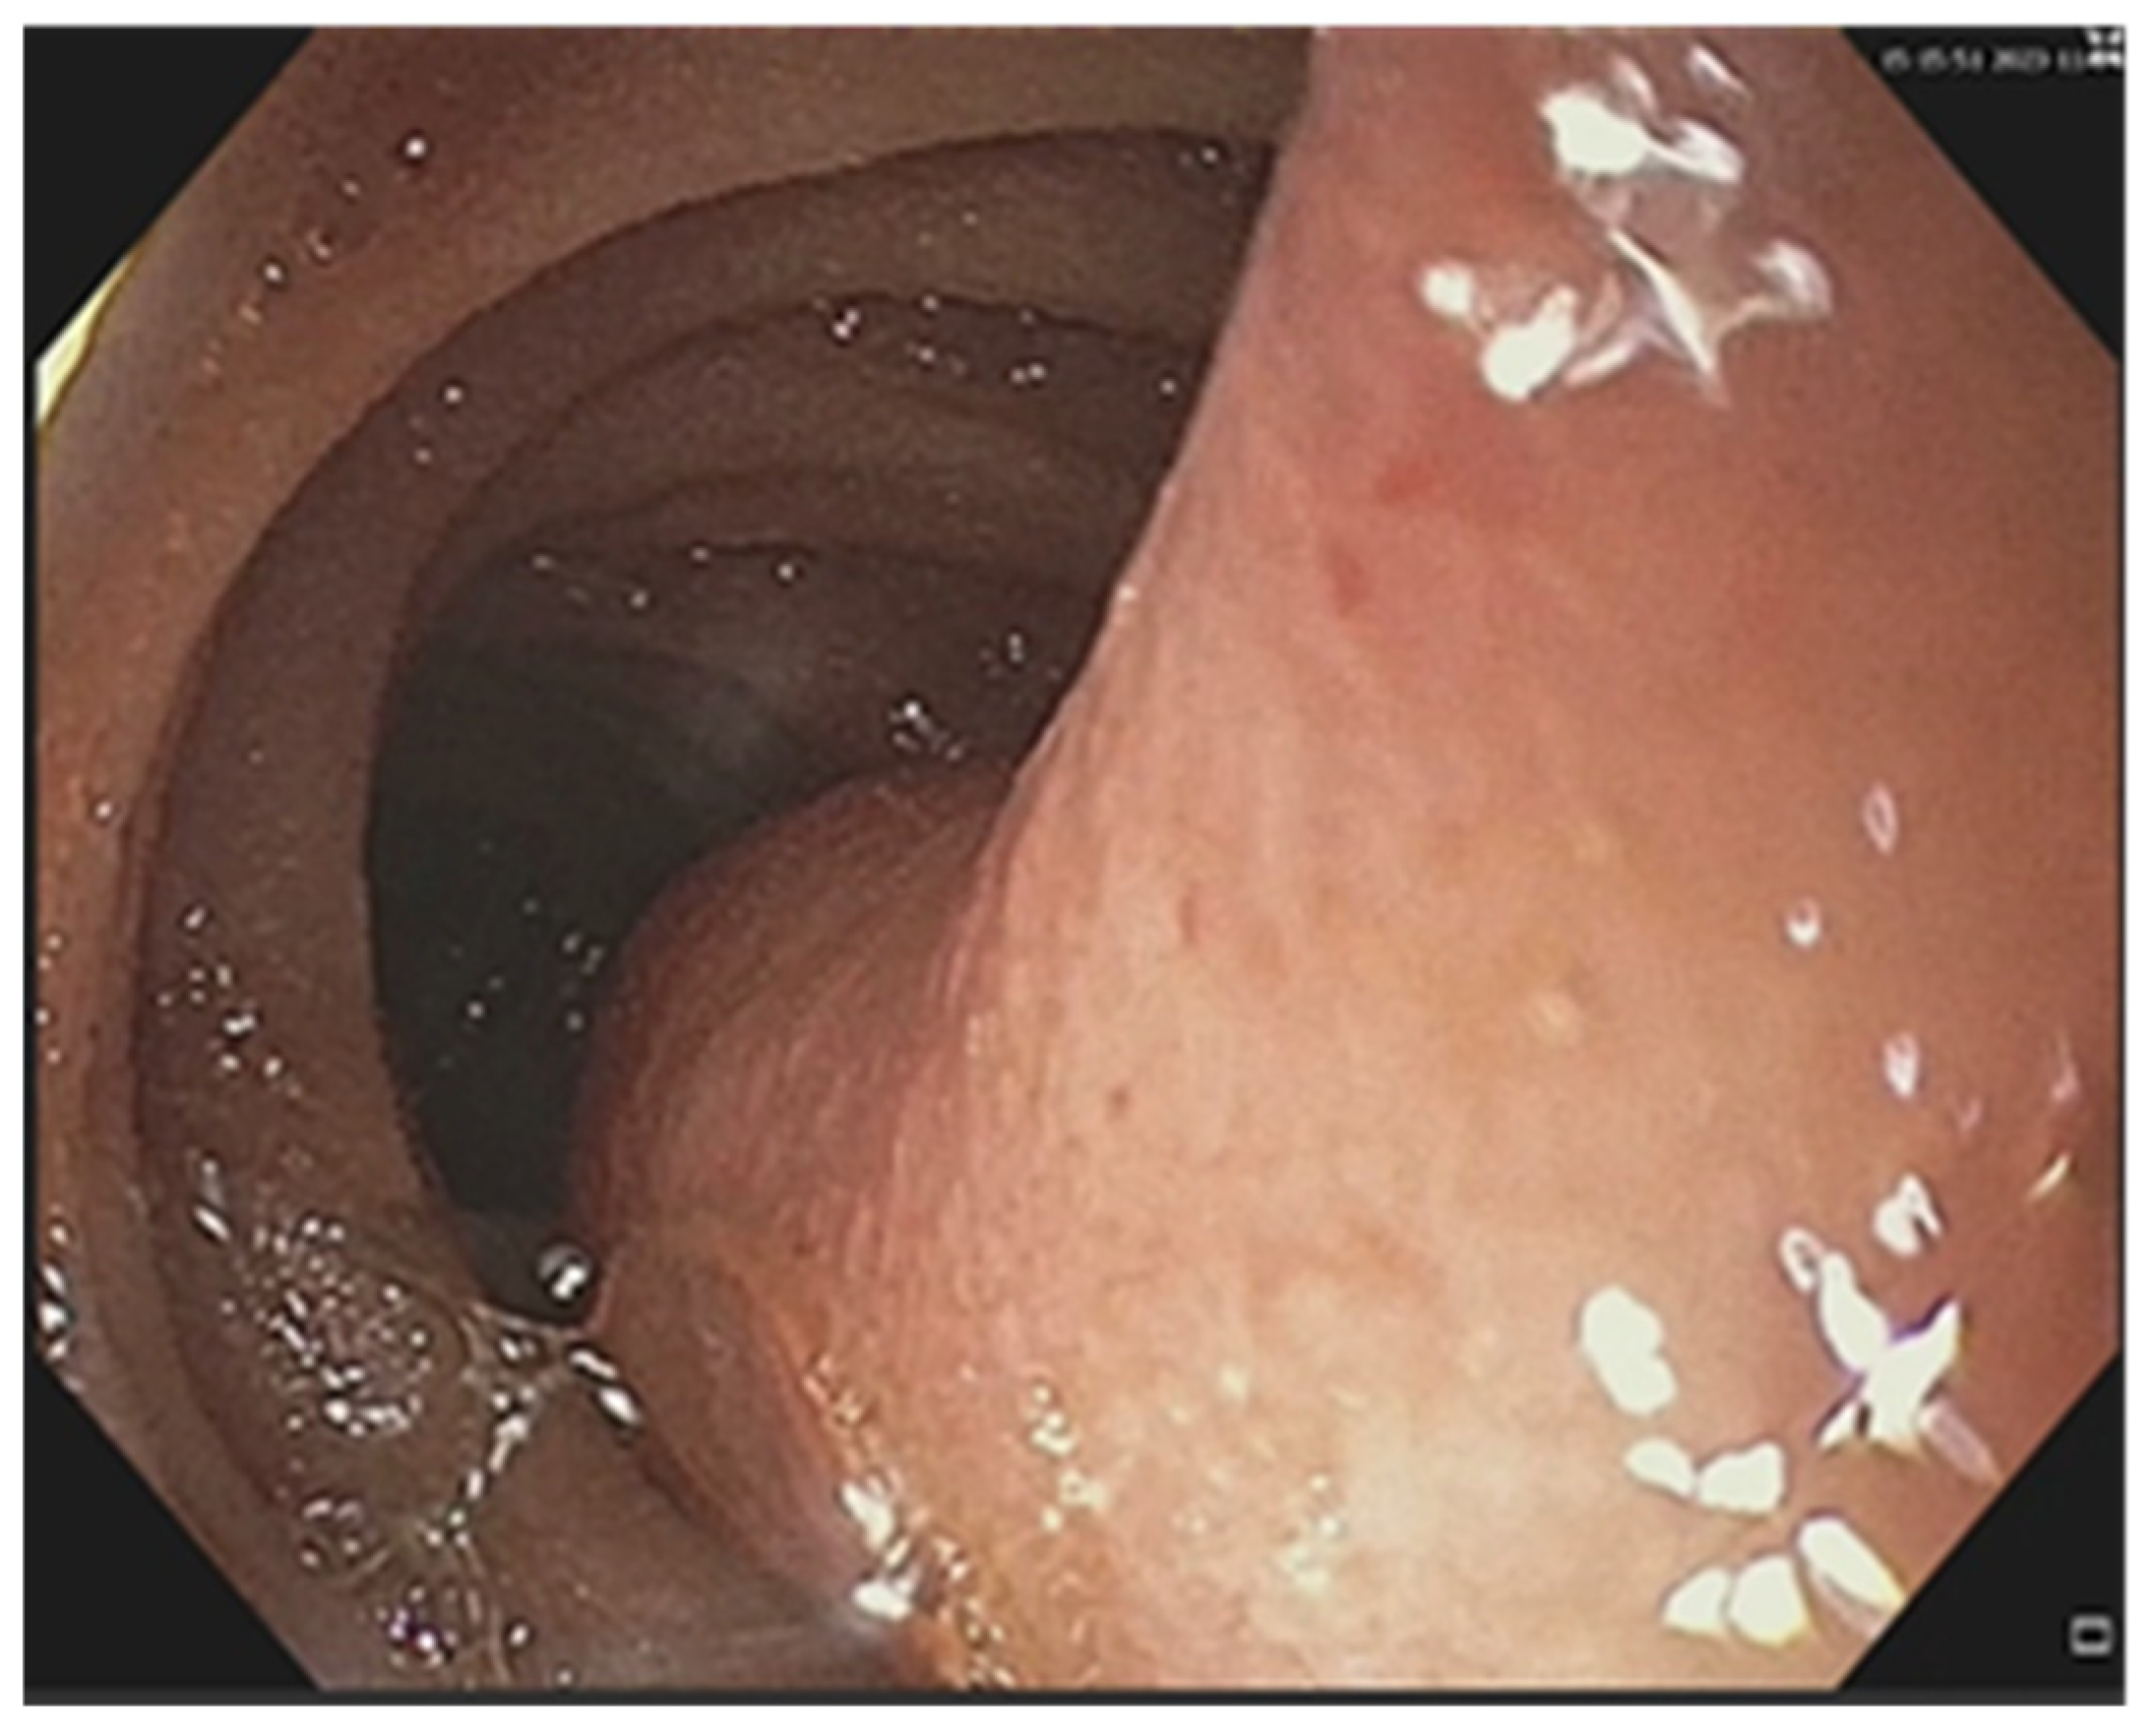

3.2. Treatment Particularities